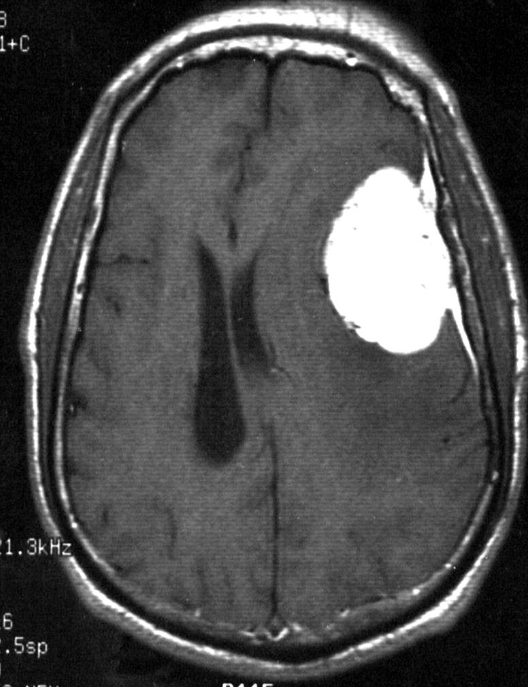

Axial T1 post contrast MRI - Meningioma MR

- Dural based

- Homogenous enhancement [Gd- DTPA] [Dural tail]

A. Give the name of the pattern of contrast enhancement of the lesion in the given image. oval mass in the left parietal region, with well-defined borders, appears hypointense to grey matter on the T1 & hyperintense on T2-weighted image.

B. Give ONE cause for the pattern of contrast enhancement shown in the given image Meningioma